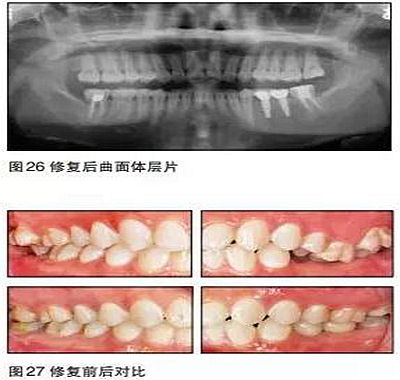

最后修復(fù)體在口內(nèi)就位,35N鎖緊螺絲,封閉螺絲口,納米樹脂充填螺絲開口,調(diào)牙合,拋光完成。

在本病例中,患者的主觀愿望是想通過(guò)種植來(lái)修復(fù)缺失牙。口內(nèi)檢查及口腔曲面體層片顯示患者缺牙區(qū)的骨質(zhì)良好,骨量充分,但咬合情況非常復(fù)雜。如果不先通過(guò)正畸治療來(lái)改善咬合而直接進(jìn)行種植手術(shù),那么后期的修復(fù)將異常困難。

35、36種植時(shí)采用骨水平的NobelActive植體;由于植體位置比較理想,修復(fù)體采用螺絲固位的氧化鋯基臺(tái)一體冠,便于今后牙冠及種植體的維護(hù)。最終種植修復(fù)完成后在咬合、美觀、牙齦乳頭充盈等方面都取得了滿意的效果。